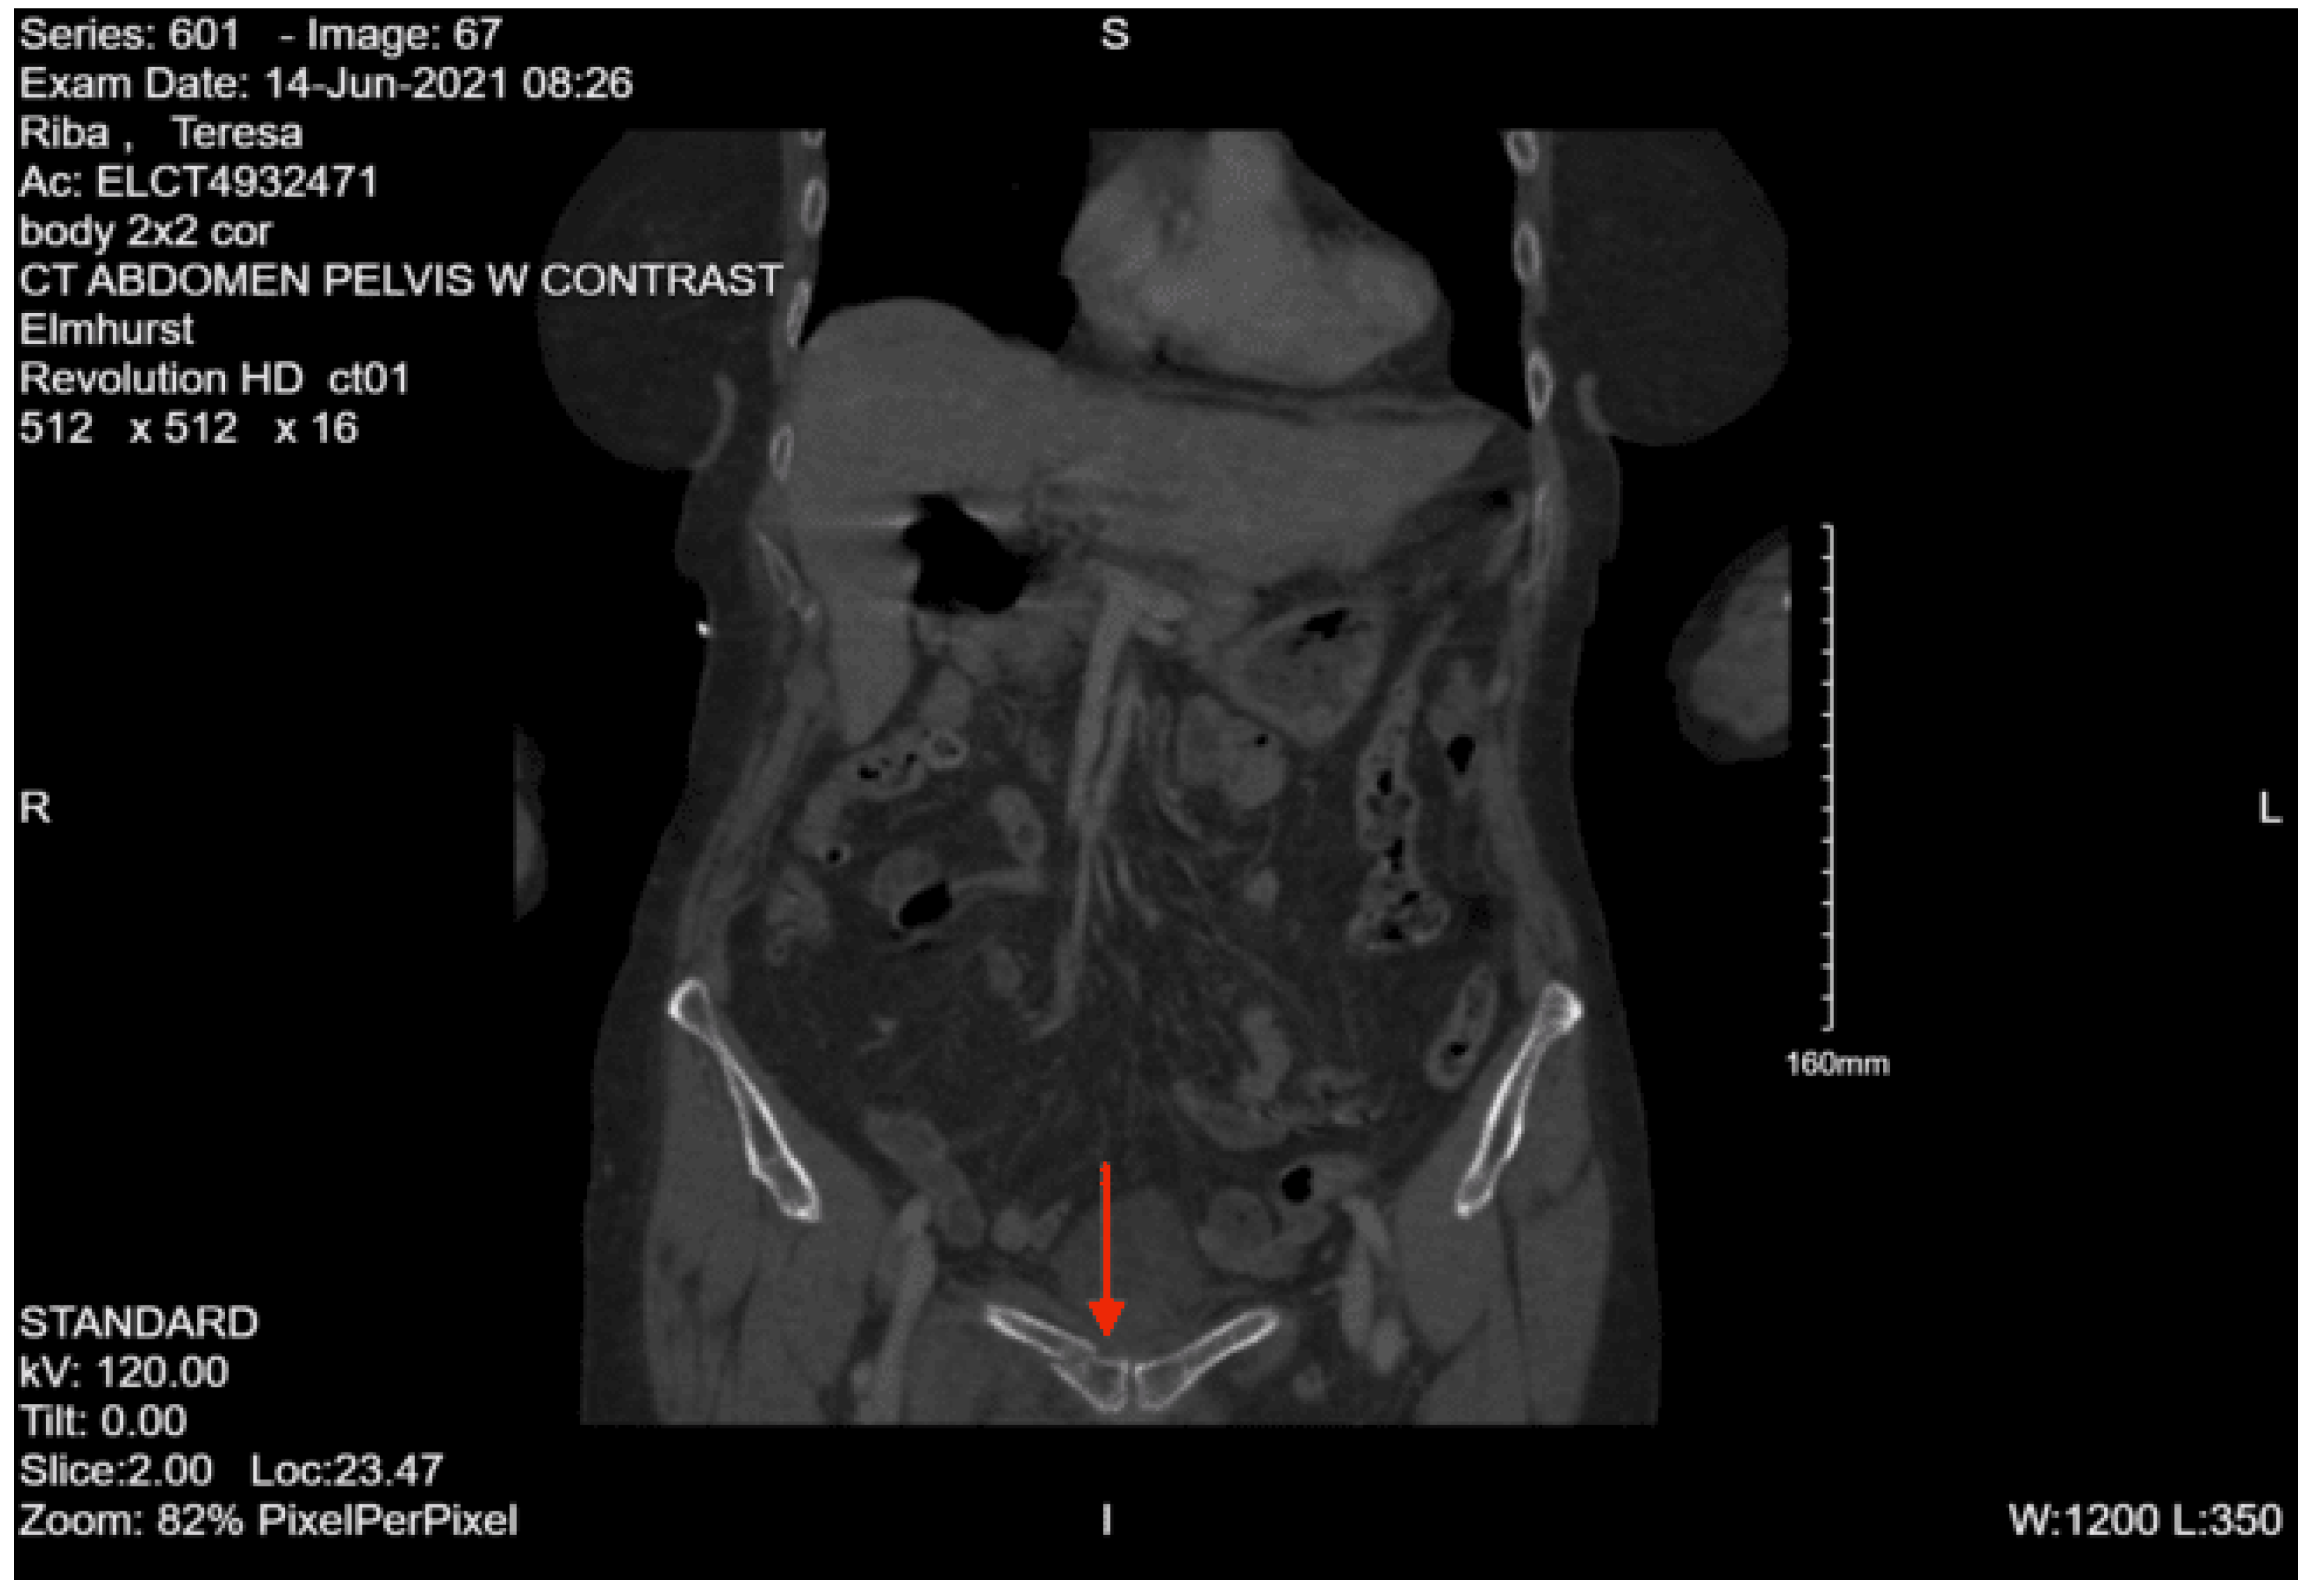

Imaging as shown in Figure 4, Figure 5 and Figure 6:

Portable pelvis x-ray: Acute impacted fracture involving the left superior pubic ramus in its medial aspect. Possible fracture, which is nondisplaced, involving the left inferior pubic ramus. The right superior and inferior pubic rami are intact. Femoral acetabular joints were unremarkable.

CT abdomen and pelvis with contrast: No acute visceral traumatic abnormality. There is evidence of an acute impacted fracture involving the left superior and inferior pubic rami. The right superior and inferior pubic rami are intact. The sacrum and coccyx appear unremarkable.

During her hospital course, the patient was also found to have a right lateral tibial plateau fracture and bilateral sacral ala fractures; orthopedic surgery recommended non-weight bearing for the RLE, and neurosurgery recommended bed rest. She required multiple blood transfusions due to repeated drops in hemoglobin/hematocrit but remained hemodynamically stable. Given her continued intubation status, tracheostomy was performed on hospital day 8. Continued monitoring via CT head with and without contrast continued to show evolving strokes and persistent severe vasospasm. On hospital day 13, the patient was seen by physical medicine and rehabilitation, who recommended physical and occupational therapy and TBI unit vs sub-acute rehab for discharge when the patient was medically stable. The patient’s mental status gradually started to improve, and she was transferred to the surgical stepdown unit on hospital day 15. On hospital day 19, PEG was placed by interventional radiology. The patient continued to slowly improve, and tracheostomy decannulation was performed on hospital day 36; then she was discharged to TBI rehab 3 days later.